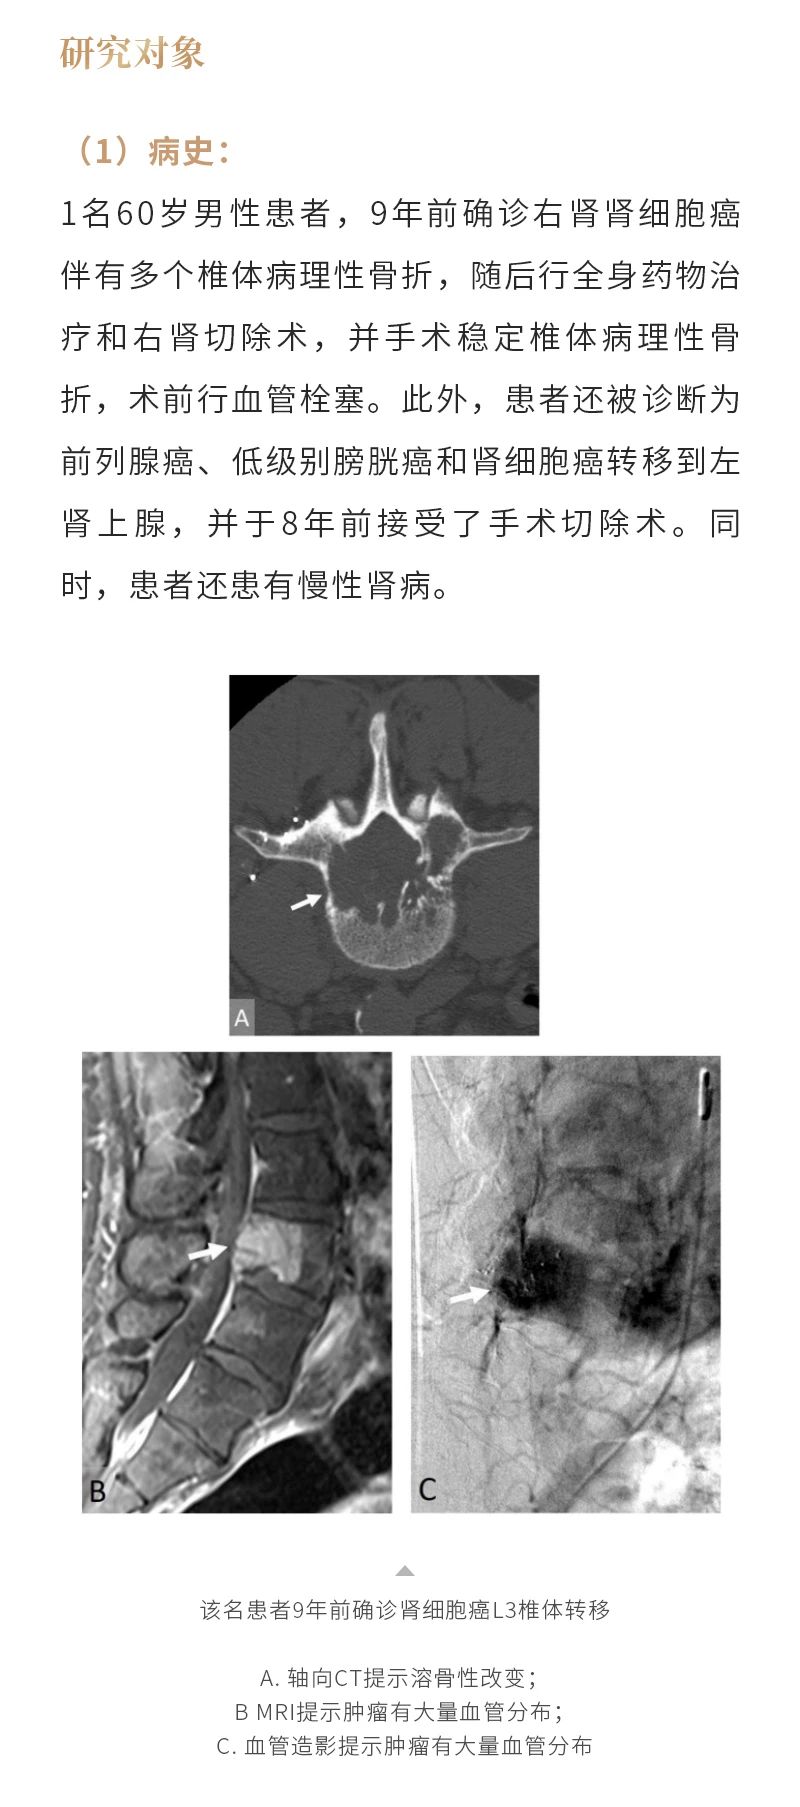

冷凍消融骨腫瘤——【海杰亞科研資訊】第285期